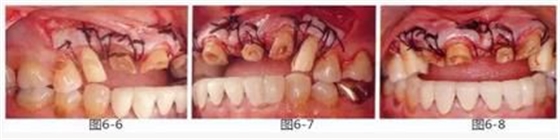

圖6-6~8

左上3到右上3的牙齒,通過(guò)包含牙槽骨外科處理在內(nèi)的APF進(jìn)行治療,確保了獲得biologic width所必需的、3mm以上的健全牙體組織。為獲得附著齦,使用FGG對(duì)左上4和右上4的牙齒進(jìn)行了治療。